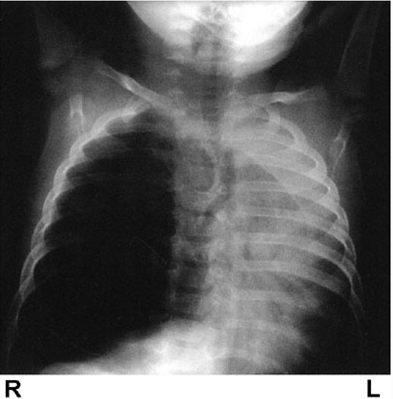

Last, a 4-year-old boy with asthma comes in with an acute exacerbation and despite treatments he becomes acutely worse (extreme resp distress, BP 50/20) and has poor air movement on left, and no wheezes. Xray shows this:

Question asks what is "most likely underlying cause of this patient's hypotension. Narrowed it down to "atelectasis of the left lung" vs "decrease in cardiac output" (correct). I thought the severe atelectasis was causing the decreased CO, and thus was the "underlying cause" ... am I missing something?

He has a tension pneumo